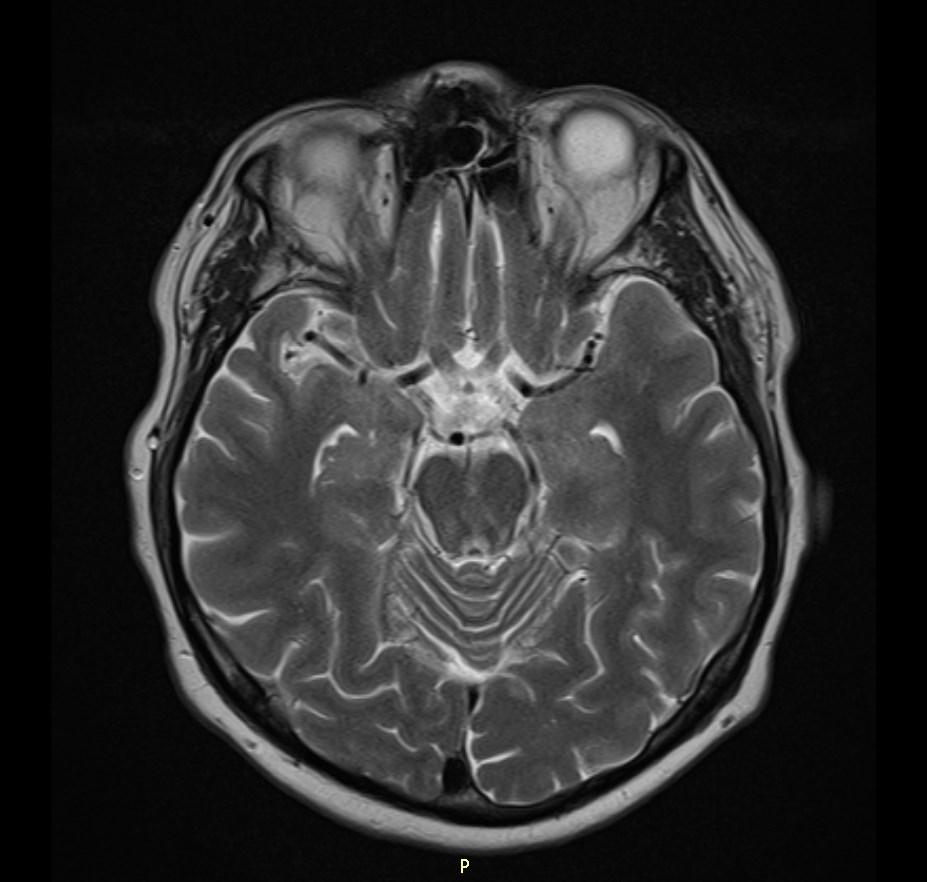

MRI images revealed hyperintensities in the periaqueductal region and the medial thalami.

MRI

T2/FLAIR: symmetrically increased signal intensity in the mamillary bodies, dorsomedial thalami, tectal plate, periaqueductal area, and around the third ventricle.